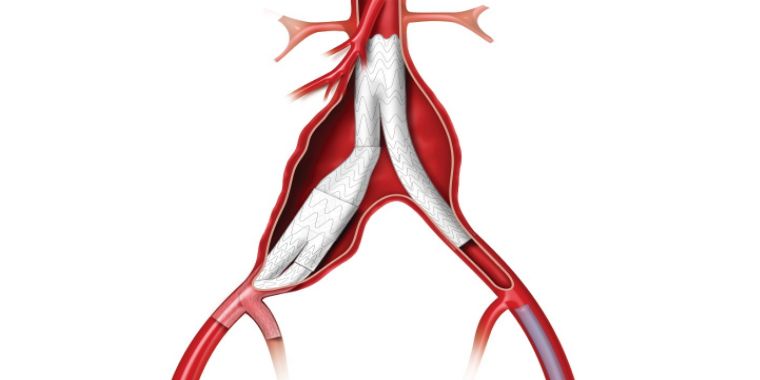

大動脈解離は、突然発症する疾患で、大動脈に亀裂が入り、血管が裂ける病気です。急性期には解離した血管壁が薄くなり、破裂を起こす可能性や主要臓器への血流が遮断されることで臓器障害を引き起こす可能性があります。治療法は、動脈瘤と同様に人工血管置換術とステントグラフト内挿術があり、病態に合わせて適切な治療を行います。

当院では大動脈解離の治療法にオープンステントグラフトを導入しています。オープンステントグラフトは広範囲の解離部分に対して治療効果が得られる利点があります。

解離した場合によっては、ステントグラフト治療が適応になることがあります。大動脈解離に対するステントグラフト治療は専門性が高く、心臓血管に特化した当院の大動脈専門スタッフが慎重に判断して施行しています。

白矢印が大動脈の亀裂、赤矢印はステントグラフトで亀裂を閉鎖していることを示す。